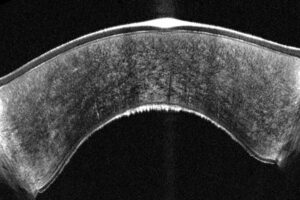

- Averaging-modus voor “Optische biopsie”**

- Epitheliale diktemapping